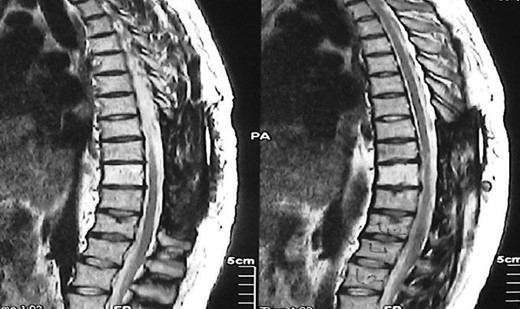

A 30-year-old male patient was admitted to our clinic with back pain. Pain was provoked by movements. The severity of pain was associated with the inability to perform the activities of daily living. The patient did not have any lymphoma-related B-type symptoms, including body weight loss, fever and sweat at night. He did not have a past and family history. There was no neurological deficit. Routine laboratory test results were normal. A magnetic resonance imaging (MRI) scan of the thoracic spine demonstrated an epidural tumor at the T9–11 level (Figs 1–3). The patient underwent spinal cord decompression via total laminectomy of T9–11 levels. Subtotal resection of the tumor was performed. Histological examination revealed the polymorphous cellular infiltration by histiocytes, large mononuclear cells and lacunar Reed–Sternberg cells with folded multi-lobed nuclei and small nucleoli (Fig. 4). Immunohistochemical staining was positive for CD15 and CD30 and negative for CD3, CD20, CD79a or CD45Ro. These features were most frequently observed in the mixed cellularity type of Hodgkin's lymphoma. Histological examination of the vertrebral body revealed no abnormality. The results of all other examinations (F-18 fluorodeoxyglucose positron emission tomography (F-18 FDG PET/CT), bone marrow biopsy and computed tomography (CT) of the chest, abdomen and pelvis) were negative for an occult disease. The patient was referred to the hematology department to undergo staged treatment. Six courses of chemotheraphy containing ABVD regimen (adriamycin, bleomycin, vinblastine and dacarbazine) were given to the patient. Postoperative MRI scan did not reveal any evidence of Hodgkin's disease (Fig. 5), F-18 FDG PET/CT, CT of the chest, abdomen and pelvis were obtained in 24 months and did not reveal any evidence of Hodgkin's disease.

Postoperative MRI scan did not reveal any evidence of Hodgkin's disease.

Moridaira et al. [4] reported a case of Hodgkin's disease at T8–10 epidural space. Rao et al. [6] published a case with primary spinal epidural Hodgkin's lymphoma. Our case is apparently the seventh case to be diagnosed with Hodgkin's disease who presented with spinal cord compression due to epidural space without lymphoma elsewhere. The abnormal MRI marrow signal of the T9 and T10 vertebral bodies can be seen in Fig. 5. Maybe the tumor in fact originated within the abnormal T9 or T10 bone marrow and spread to the epidural space via the epidural venous plexus. But histological examination of the vertebral body revealed no abnormality.